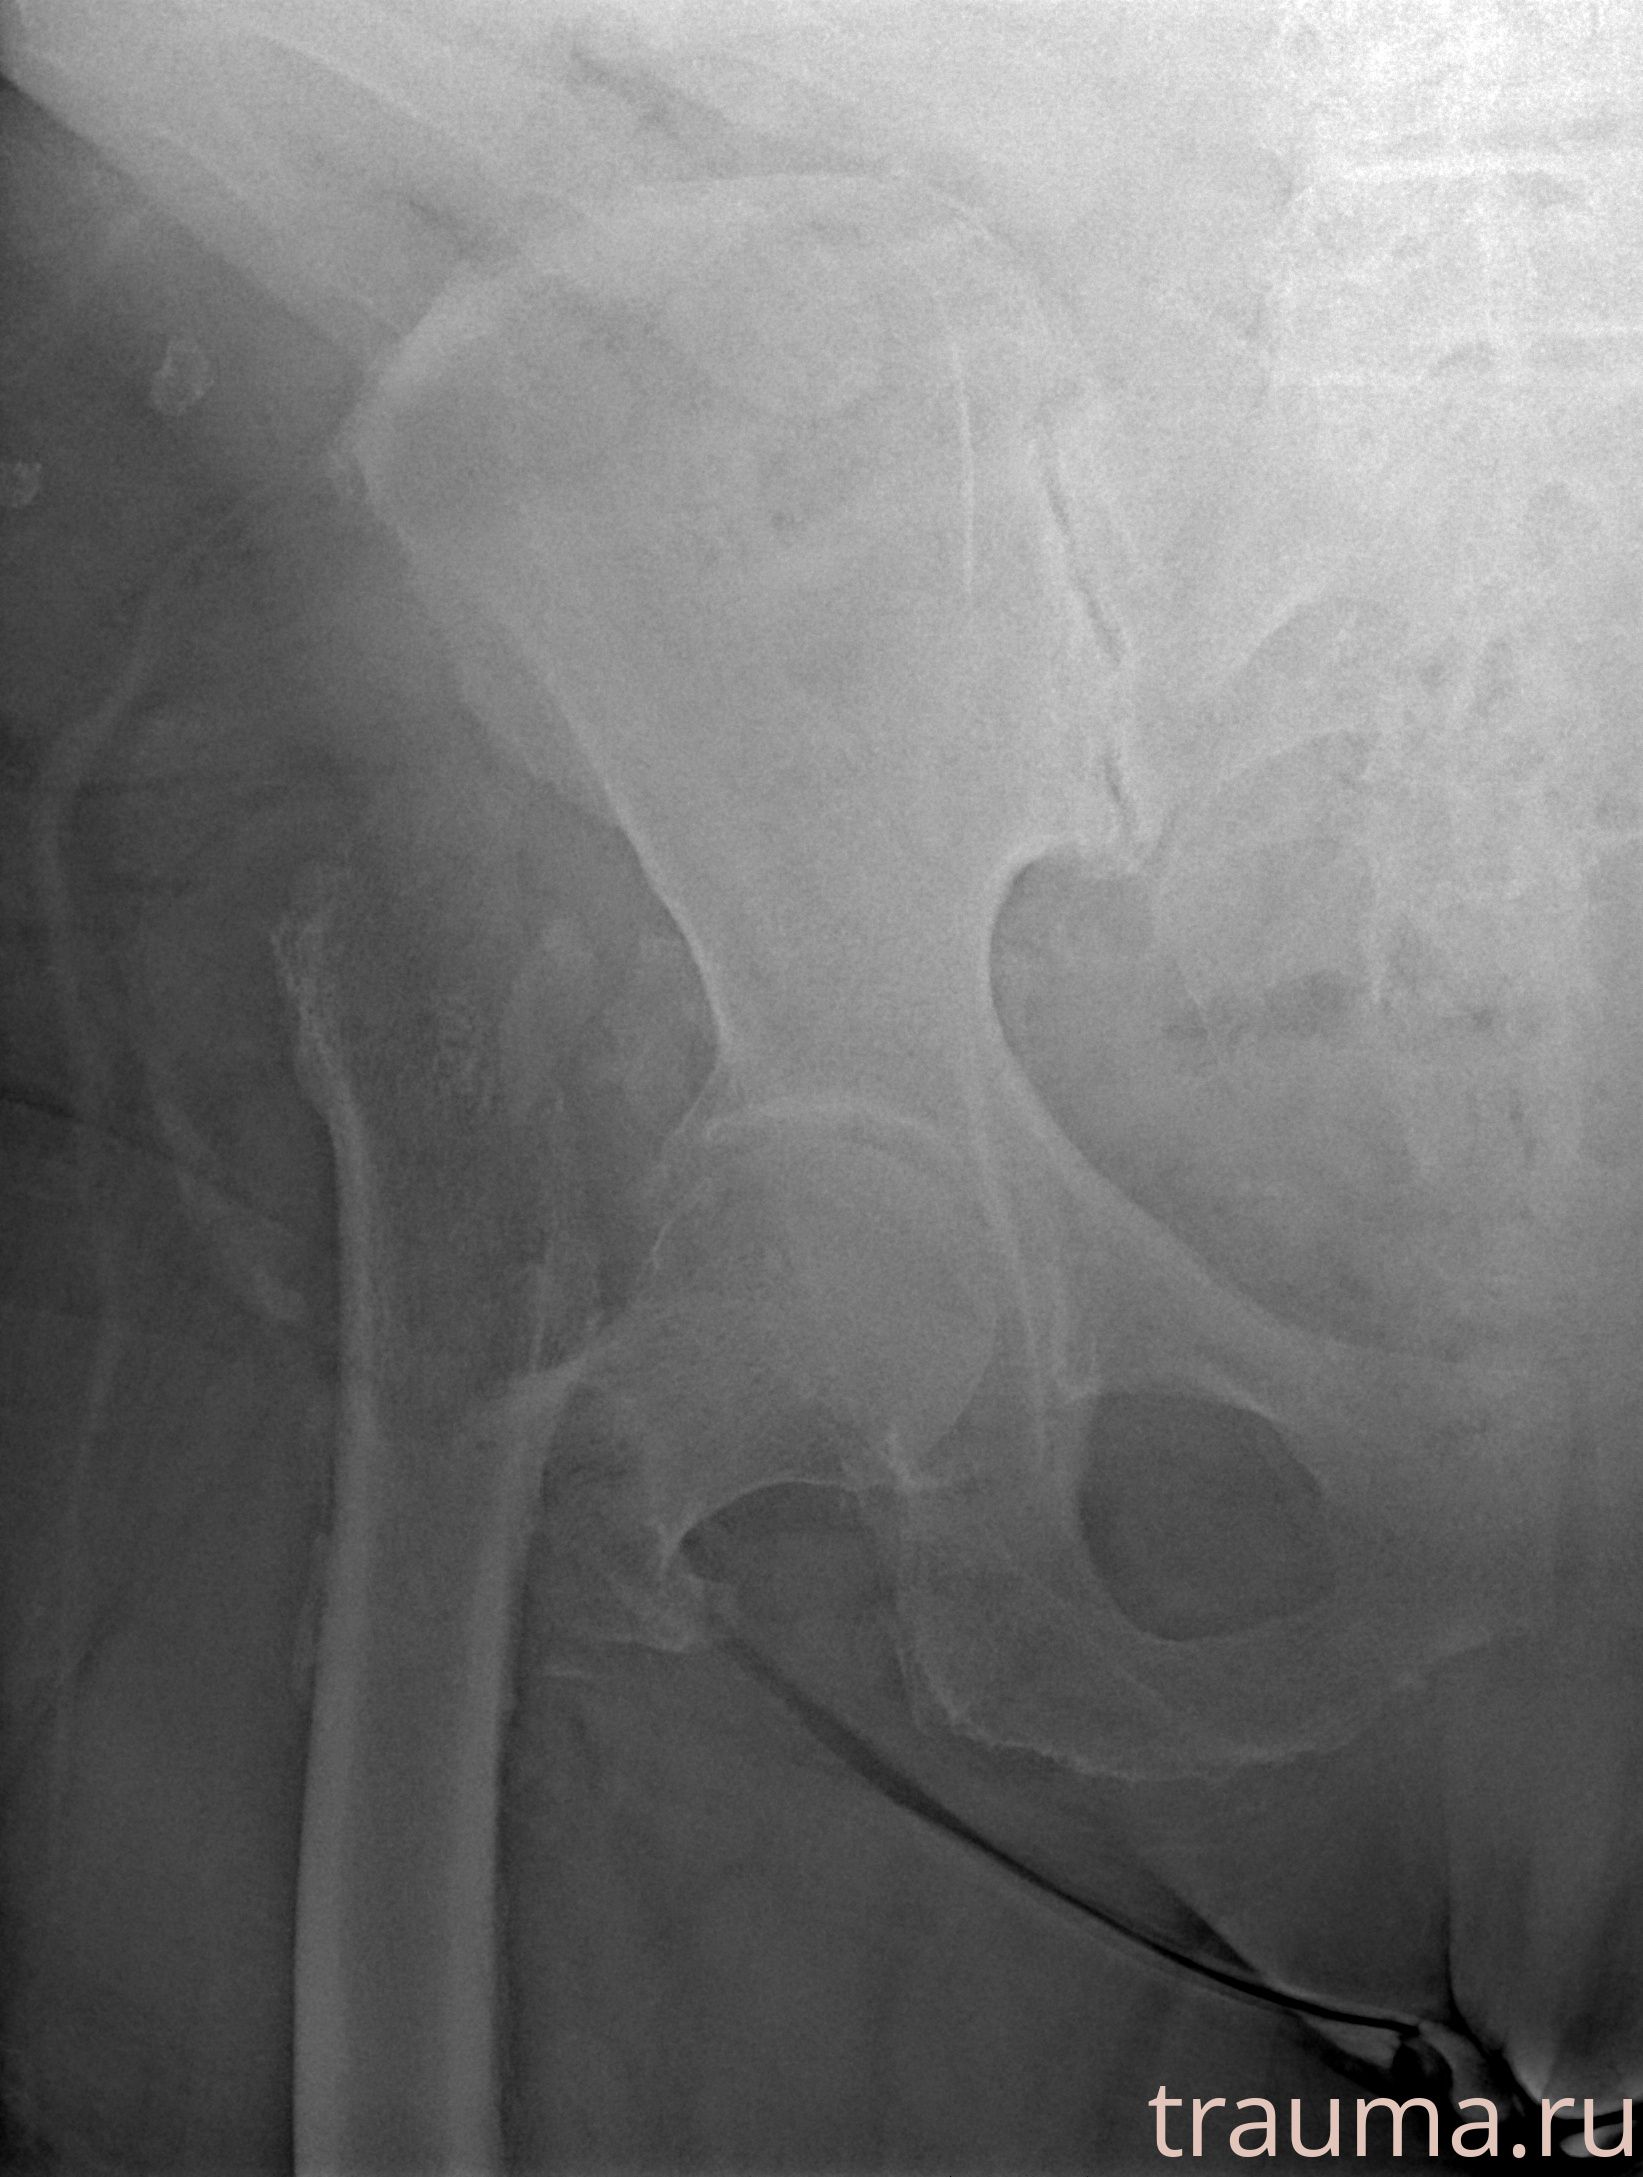

Рентгенограммы

Рентген на дому: по вашему адресу приезжает врач-рентгенолог, травматолог-ортопед с мобильным рентгеновским аппаратом, проводит диагностику травмы или заболевания, делает необходимые рентгенограммы, дает рекомендации по дальнейшему лечению. Получить качественные снимки в домашних условиях возможно благодаря уникальной методике, разработанной МосРентген Центром для института  Склифосовского

Яркость: 1   Контраст: 1   Инвертировать: 0 Увеличение: 1

Перетаскивайте мышь вверх/вниз для контраста, влево/право для яркости. Прокрутка колесом изменяет масштаб. Нажмите Сбросить для возврата к исходному изображению. При увеличении держите мышь в той области, которую хотите рассмотреть.